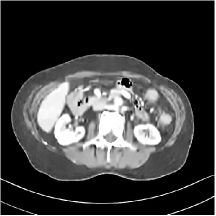

III.C. Low-dose Experiments with Mayo Clinic Data

First, we study transform training based on Mayo Clinic data. As shown in Fig. 6, seven slices obtained at regular dose from three patients are used for transform learning. The number of pixels . Similar to the phantom experiments, overlapping patches are extracted with a patch stride. The number of overall training patches is about . We set for ST, , , for MARS2, , , , , for MARS3, , , , , , , , , for MARS5, , , , , , , , , , , , , for MARS7. The iteration number in Algorithm 1. Fig. 7 illustrates the learned transforms obtained with Mayo Clinic data. Different from the XCAT phantom case, these transforms up to MARS5 display more complex features and structures. The rich features of the MARS models better sparsify the training images over layers compared to the single-layer model (ST).

III.C.2. Simulation Framework, Reconstruction Results, and Comparisons

The synthesized low-dose clinical measurements are simulated from regular-dose images at a resolution of mm with a fan-beam CT geometry corresponding to a monoenergetic source at incident photon intensity . The sinograms are of size . The width of each detector column is mm, the source to detector distance is mm, and the source to rotation center distance is mm. We reconstruct images of size with the pixel size being mm mm.

We conducted experiments on one test slice used for parameter tuning (L067-slice 120) and four independent test slices (L109-slice 90, L192-slice90, L333-slice140, L506-slice 100) of the Mayo Clinic data. For PWLS-EP, we ran iterations using relaxed OS-LALM and set regularization parameter . We used the same as the phantom experiments for Algorithm 2. The process of selecting a general set of reconstruction parameters () for the Mayo Clinic test slices is identical to that for the XCAT phantom in Section III.B.2. The selected regularization parameter and the parameters that control the sparsity of the coefficient maps are for ST, , , , , for MARS2, , , , , , , for MARS3, , , , , , , , , , , for MARS5, and , , , , , , , , , , , , , , for MARS7, respectively.

Figs. 8, 9, 10, and 11 show the reconstructions of the four independent slices using the FBP, PWLS-EP, PWLS-ST, PWLS-MARS2, PWLS-MARS3, PWLS-MARS5, and PWLS-MARS7 schemes, respectively. Additional Mayo Clinic experimental results of the parameter tuning case (Fig. 15) are shown in the supplementary document. Table 1 lists the RMSE and SSIM values of reconstructions of the four independent test slices, with the best values bolded. Generally, the five and seven layer models provided the best RMSE and SSIM values. They outperform the single-layer model by HU in RMSE on average. However, the MARS5 and MARS7 models perform similarly. In order to strengthen the benefits of the multi-layer model, Table 2 lists the RMSE of the reconstructions in four different ROIs (shown in the reference of Fig. 11) with seven methods for slice 100 of patient L506. By observing the reconstructed images, we see that although the ST model achieves a cleaner reconstruction result than FBP and PWLS-EP, it still sacrifices some sharpness of the central region and suffers from loss of details. The deeper models have a somewhat more positive effect in terms of maintaining subtle features, which is clearly more essential to clinical diagnosis. Furthermore, as we will discuss later, after considerable parameter tuning, we found that the information contained in residual maps is gradually decreased with the number of layers, eventually vanishing at some layer, which suggests that very deep unsupervised models might not offer significantly better image quality.